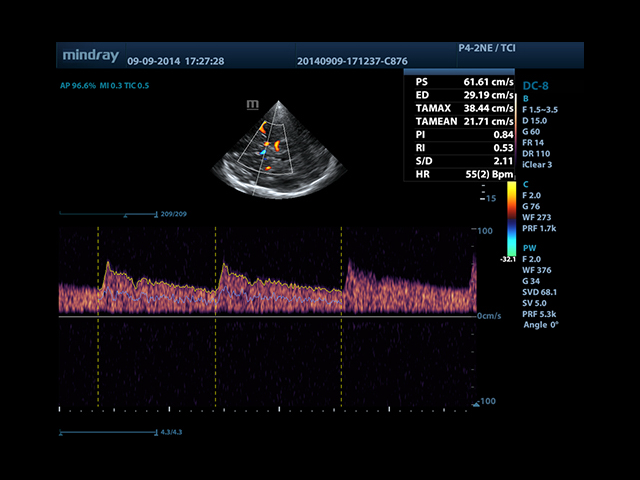

• Smart Doppler - автоматическая подстройка расположения рамки цветового доплера и контрольного объема импульсно-волнового доплера нажатием кнопки.

• Smart Doppler™ - автоматическая подстройка расположения рамки цветового допплера и контрольного объема импульсно-волнового допплера